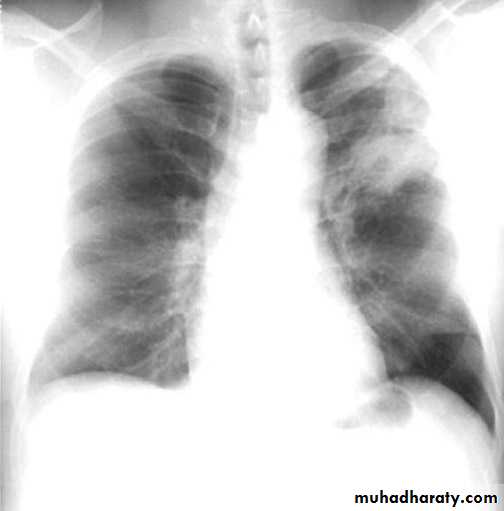

NORMAL PA view